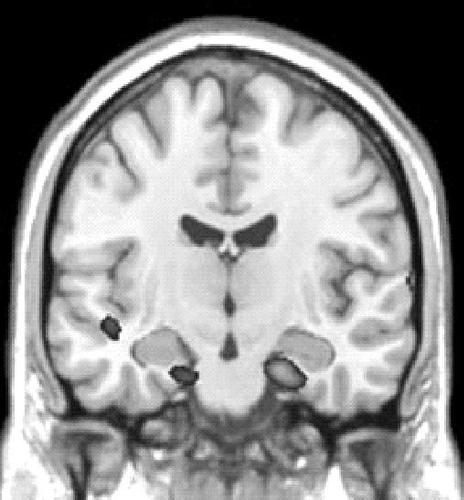

《科学》杂志发表了相关实验的结果。在实验中,志愿者被要求记住某些成对的图片,其中一张是人的面孔,而另一张是令人不安的场景——车祸或正在进行中的外科手术。随后,研究人员会向志愿者展示面孔的图片,并要求他们选择记住这张图片或试图抵制另外一张糟糕的图片。通过功能性磁共振成像(fMRI)对大脑反应进行分析后,科学家们发现,当人们成功地“忘记”记忆时(这在此后的记忆测试中证实),脑部某些区域的活动受到了抑制。这些区域包括与记忆与情感关系密切的海马回和杏仁体等。

同时,研究人员还发现,当志愿者被要求反复抑制相同的记忆时,脑部活动的模式会随时间而改变。大脑的记忆中心——海马回区域的活动在后期实验中逐渐减少,提示“在抑制记忆活动之前,它可能需要一点恢复。”麻省理工学院神经学教授约翰·加布莱里(John Gabrieli)如是推测说。

在后期实验中,与认知控制有关的大脑前额叶区域活动水平有所升高。加布莱里认为,这提示前额叶正在学习如何对大脑的记忆区域进行控制。